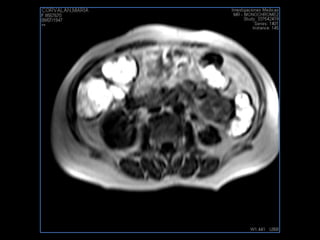

LIC ALEJANDRA GALVEZ RM DE ABDOMEN

PROTOCOLO abdomen COR T2, AXIAL supresion grasa AX T1 +SAG T2  CON   GADOLINIO :  COR T1+AX T1(DIN) SAT: NO  FASE: RL THK: 6MM  COIL:  GAP: (FACTOR 1.4) 2MM FOV: 40 CM NEX:2 SINCRONIZACION RESPIRATORIA EN 3 O 4 CICLOS ALE

resonancia de abdomen